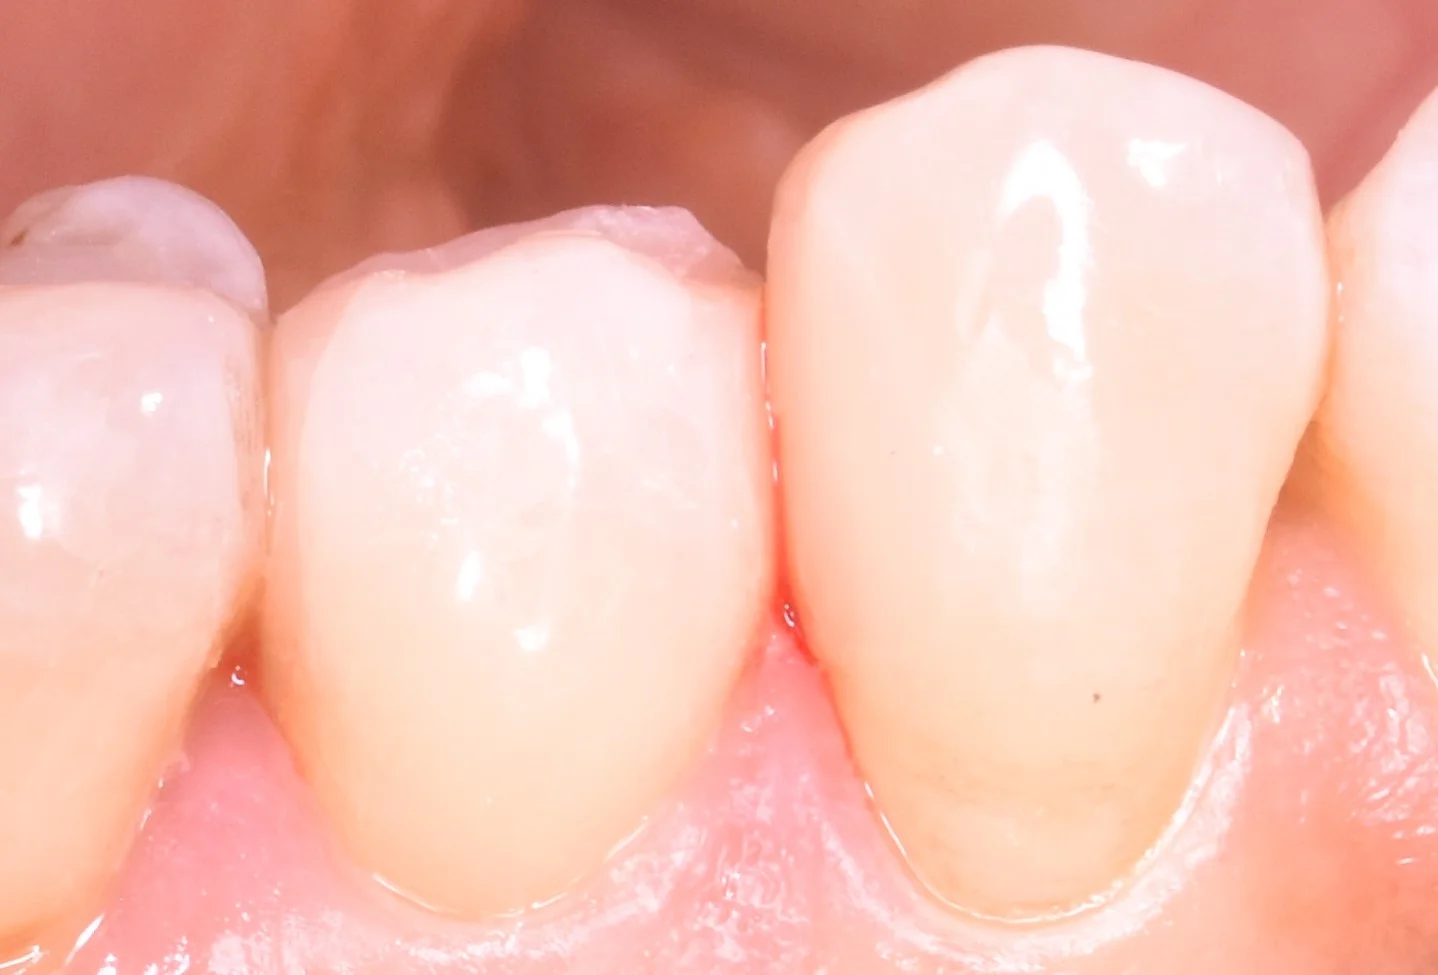

そして虫歯を詰め終わったのがこちらです。

術前の状態では手前の歯に刺さるような状況になっていたのですが、その形態だとまた虫歯になりやすくなっちゃうと思いましたので、清掃性を優先して自然な形で当たるように詰めました。

側面から見たのがこちらになります。

側面から見ても、歯と歯の間の当たりは弱くなっていないのが分かるかと思います。

(若干出血していたので、それが歯の間に毛細管現象で入り込んでますね(-_-;))